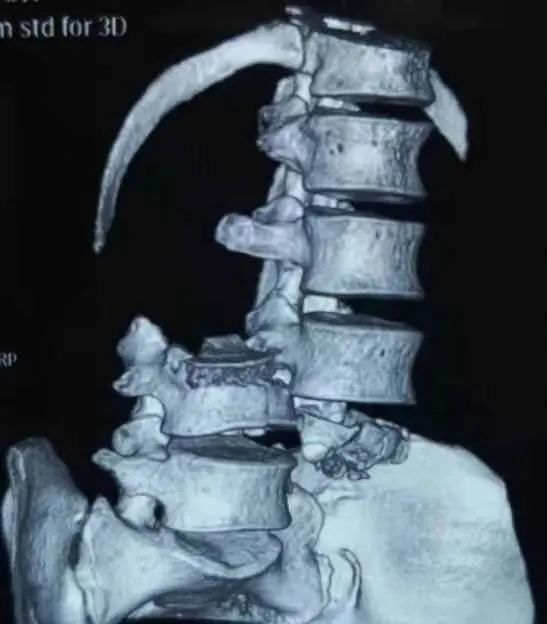

CT重建见第3和第4腰椎脱位

随后,患者直接被送入重症监护室。邵逸夫医院骨科赵凤东教授及其团队医生初步诊断,除车祸常见外伤外,患者还有一个最棘手的问题:腰椎的骨折脱位(L3-L4)及其继发的马尾神经损伤,患者双下肢感觉及活动均严重受损,大小便失禁。